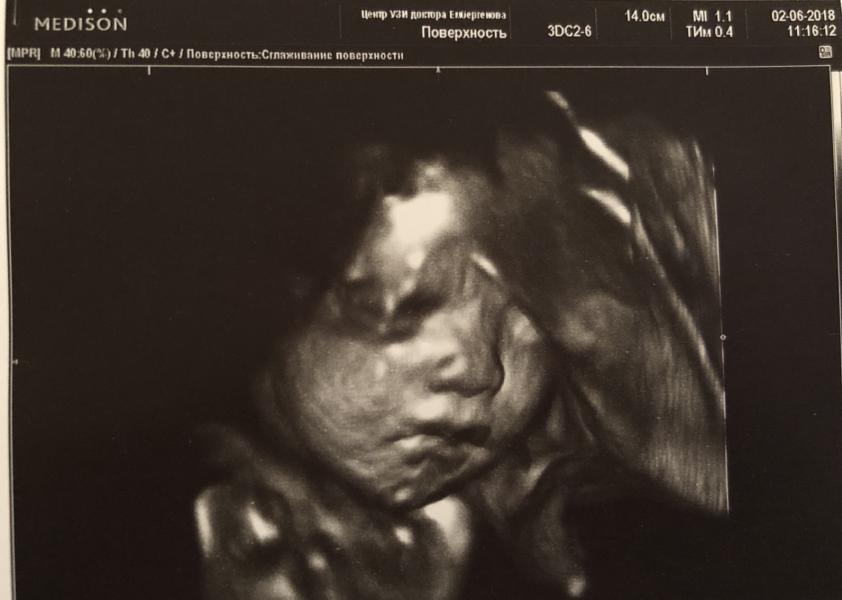

Девочки солнышки🌸 Вы просили написать после УЗИ) Всем отвечать времени нет) Утром писала, что малыш очень активный) Так вот сходила на 3д к Боренштейн) Говорю он очень активный, хоть в 3 ночи, хоть в 6 утра, постоянно говорю пинается, она говорит: ну есть же время, когда тишина? Я говорю: да, час, полчаса иногда больше, она говорит: ну правильно, сама просыпаешься будишь его, ещё и жалуешься😂 не надо все спирать на человечка, щас всё посмотрим😁В общем наконец я легла, она приложила свой аппарат ...